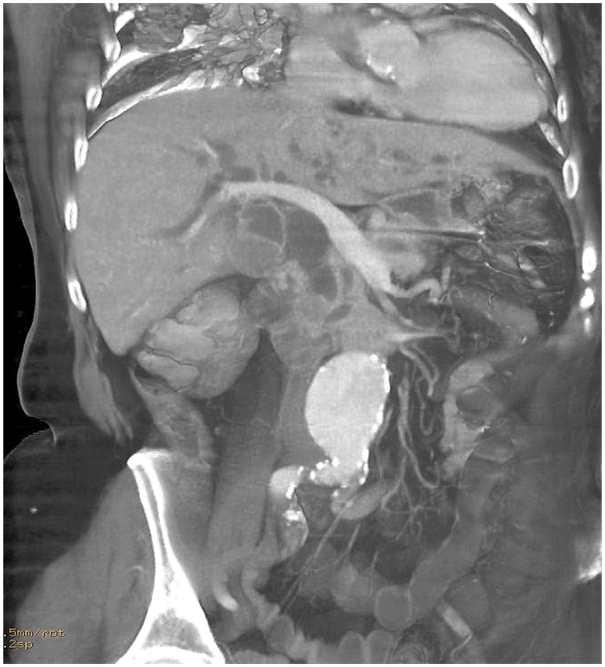

MSCT scan was performed unenhanced and on a on dynamic contrast-enhanced MDCT study with a volume of contrast medium (2mL/kg b.w) is given by rapid infusion (flow rate 4 mL/s) and MDCT is used in the parenchymal phase, with an imaging delay of aortic transit time plus 25 s, and in the venous phase (Figures 1-5). The cutoff of a distal segment of CBD and a dilatation of a CPD due to lateral compression from the pancreatic mass. The mass measured 16x10x17mm, without the infiltration of peripancreatic space. No distant metastases in the abdomen were seen, and no enlarged lymph nodes were noted.

Figure 2 Axial MDCT shows a hypoattenuating mass in the head and uncinate process of the pancreas with a dilatation of the pancreatic duct and the bile duct, and a calculus in the distal third of the gallbladder lumen.

Figure 3 Curved planar reformation shows the mass in the head of the pancreas with pancreatic duct obstruction due to the compression of its lateral wall, CBD dilatation with a curvilinear cut off sign. Fusiform aneurism of the suprabifurcational segment of the abdominal aorta with linear calcifications of the aortic wall.

In a patient with a painless jaundice on the US examination of the abdomen a dilated intra and extra hepatic bile ducts, dilated CPD were found as well as hypoechogenic focal lesion in the distal part of the head- processus uncinatus of the pancreas. Abdominal fusiform aneurysm was also visualized MSCT of the abdomen, unenhanced and dynamic contrast-enhanced MDCT study showed a hypoattenuating mass in the head and uncinate process of the pancreas measuring 16x10x17mm with a dilatation of the pancreatic duct and the bile duct -the double duct sign and a calculus in the distal third of the gallbladder lumen. No enlarged lymph nodes. No distant metastases